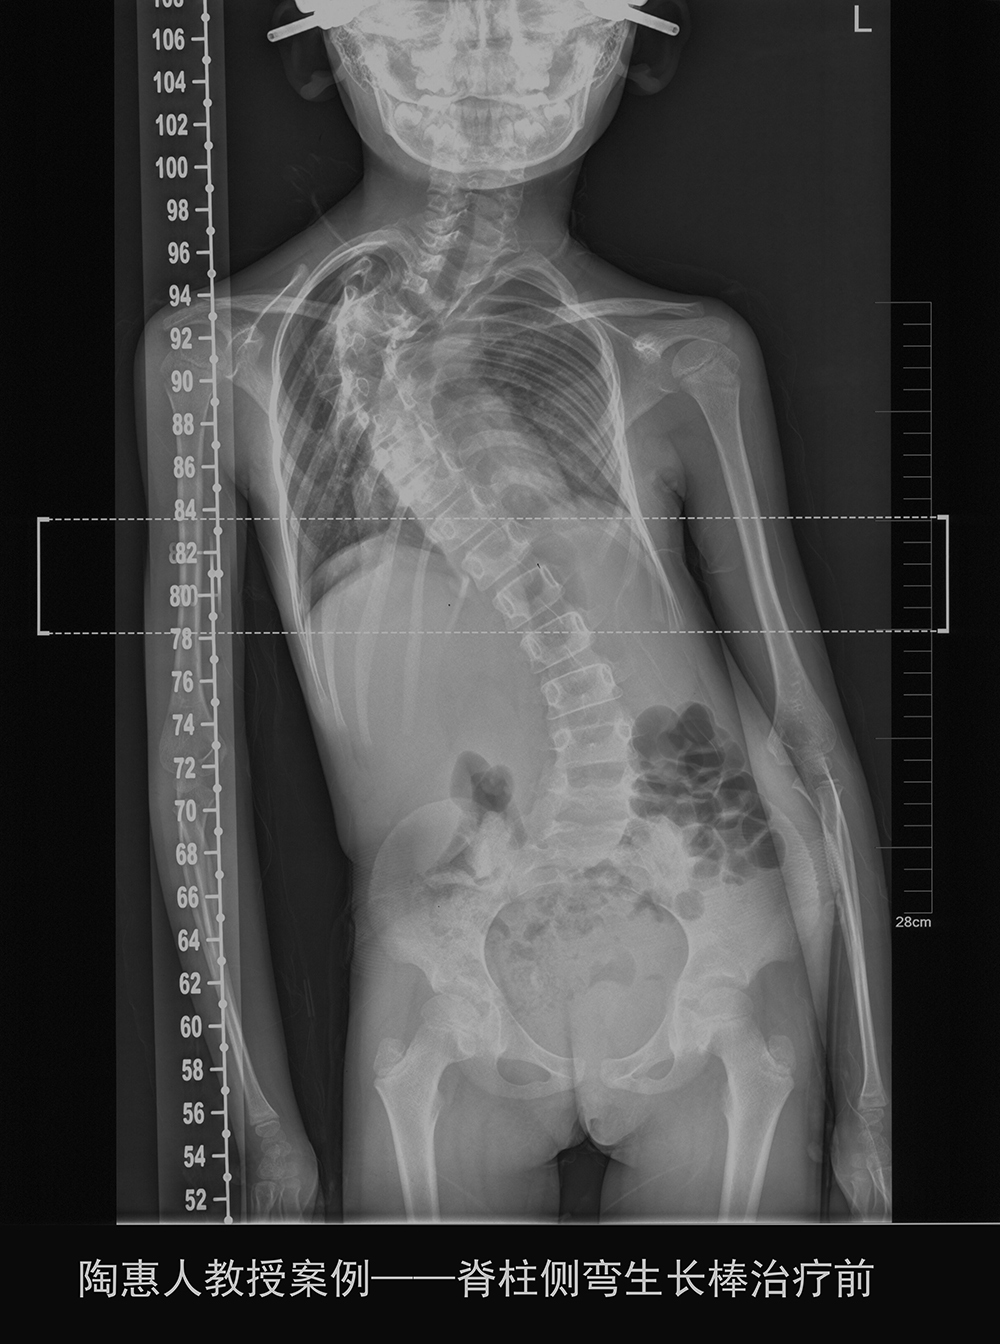

但对于先天性脊柱侧弯,尤其侧弯角度超过90度,已经严重影响生活,必须立即手术的年龄较小的患儿,可能会出现多次手术的情况。

手术时,如果直接固定脊柱,因患儿仍然处于生长发育期,让躯干保持在该年龄的长度显然不合适。因此,衍生出一种治疗方法—生长棒治疗。

生长棒治疗就是用钛合金支架将脊柱撑直,但不进行截骨,这样骨骼不会被固定。然后每年依照患者生长情况进行一次或者两次撑开操作,每次撑开几厘米,让支架随着身高增加而延长。直到患儿十几岁以后,找一个合适的时机进行最后的融合手术。